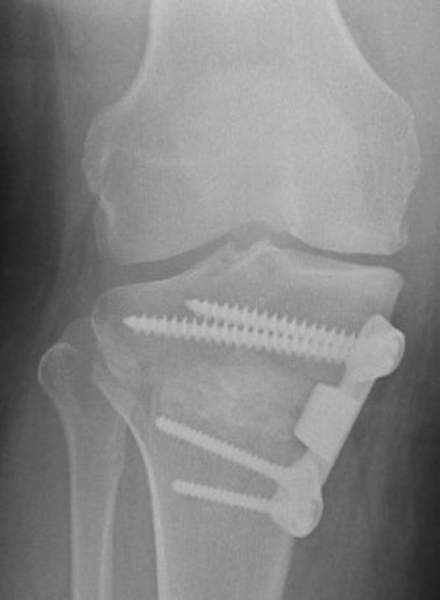

). The graduated wedge is removed, and the plate is then placed in a more posterior position. A common mistake is to leave the plate in an anterior position, which leads to an unwanted increase in posterior tibial slope. The plate is then secured with two 6.5-mm cancellous screws superiorly and two 4.5-mm cortical screws inferiorly (

Fig. 58-11

). Femoral head allograft is then morselized and placed into the wedge defect. A corticocancellous wedge is then placed just anterior to the plate to help maintain the open wedge (Fig. 58-12 and 58-13 [12] [13]). Autologous iliac crest can be used, but this can lead to donor site morbidity. Final images are obtained to ensure proper hardware placement (

Fig. 58-14

). The wound is irrigated, and the pes anserine and sartorius fascia are repaired over the plate. The subcutaneous tissue is reapproximated, the skin is closed and a dressing applied.